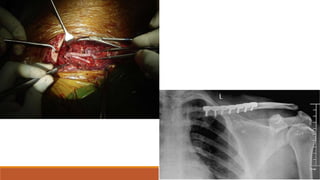

Clavicle # maybe associated with Subclavian/ brachial injury

SubclavianArtery

Right and left have different courses

Right is one of the terminal branch of brachiocephalic artery

Left arises as the third branch of the aortic arch after the left common carotid artery

Course:

Exits the thorax via the superior thoracic aperature between the anterior scalene and

posterior scalene before passing between the first rib and clavicle.

Then at the lateral border it continues as axillary artery

Parts

First part – From its origin to the medial border of anterior scalene

Second part-Posterior to anterior scalene

Third part-from lateral border of anterior scalene to lateral border of first rib